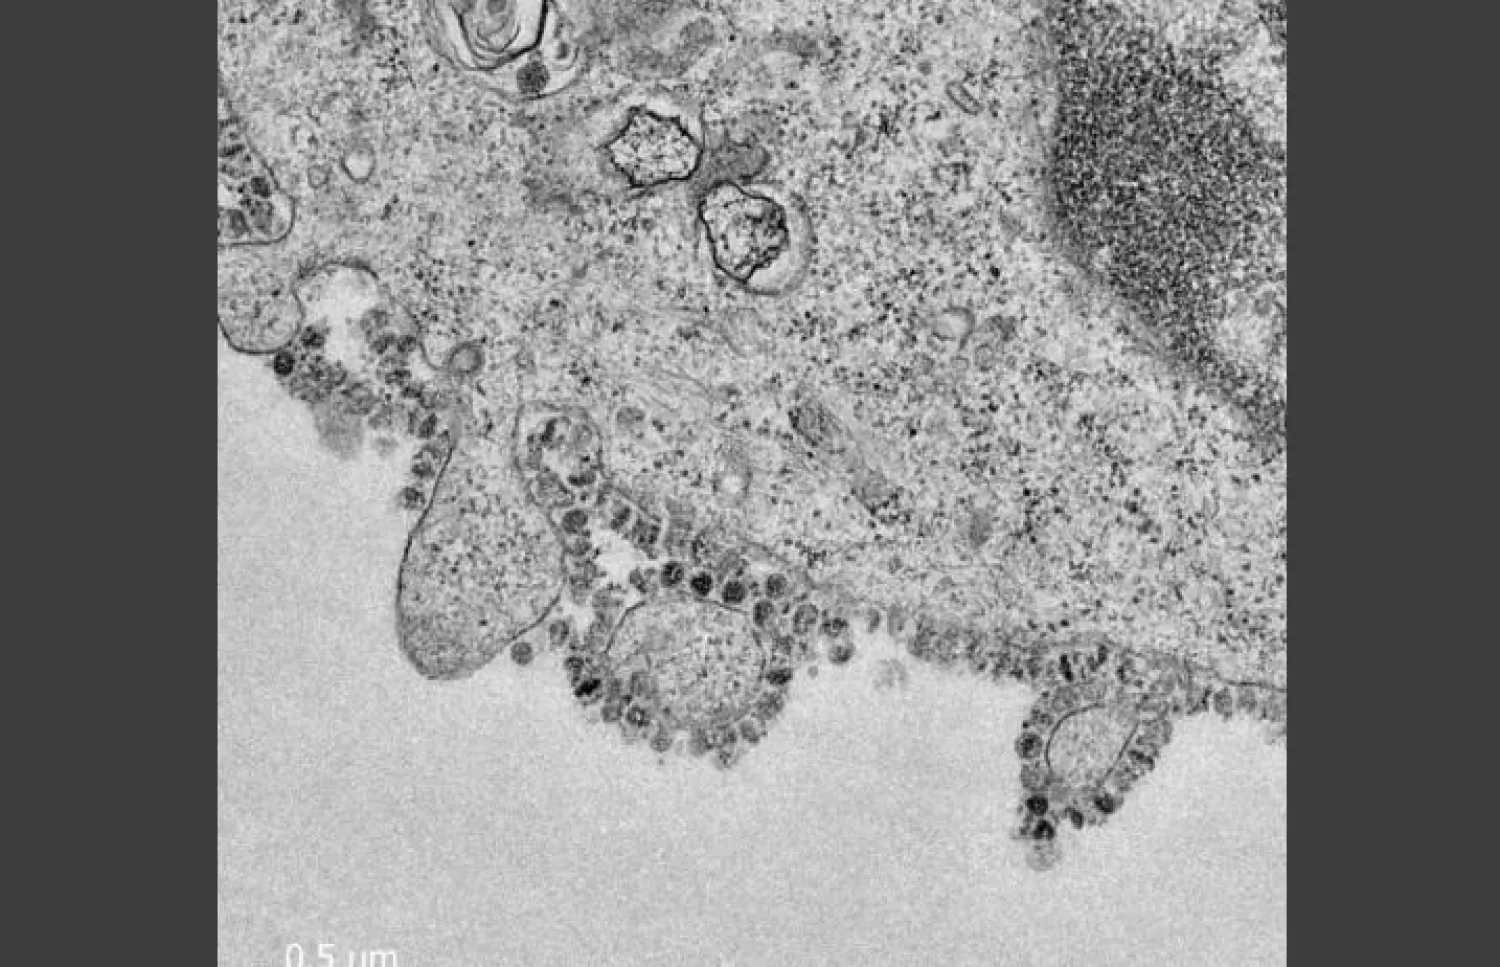

وتُظهِر صورة مجهرية إلكترونية دقيقة جزءاً من خلية مصابة بـ«كورونا»، بينما يطلق سطحها جزيئات من الفيروس، بحسب ما نشرته وكالة «بلومبرغ».

وقال جون نيكولز، وهو أستاذ في علم الأمراض (باثولوجي) في الجامعة، إن كل خلية مصابة تنتج الآلاف من جزيئات الفيروسات المعدية الجديدة التي يمكن أن تستمر في إصابة خلايا أخرى.

صورة مجهرية لفيروس كورونا الجديد ينمو في خلايا ضمن دراسة بجامعة هونغ كونغ (بلومبرغ)